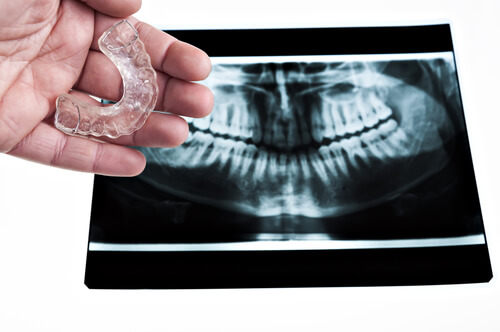

Ağız koruyucusu kullanarak, sıkma ve gıcırdatma sırasında dişlere uygulanan basınçtan korunabilirsiniz. Ayrıca yüz kaslarınızı gevşetecek masajlar yapabilirsiniz. Özellikle çene, boyun ve omuz kasları rahatlatılmalıdır.